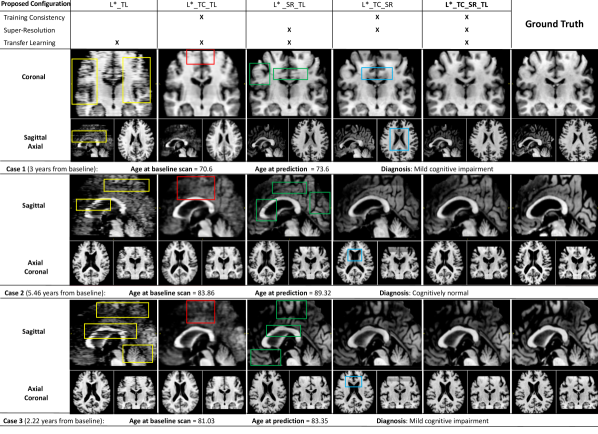

5.3 Ablation Study

The configurations of 4D-DANI-Net considered in our ablation studies involve the basic model (denoted by L∗) obtained by independent training (then stacking together) of MRI slices, plus combinations of the 3D training consistency strategy (denoted by TC and obtained when PWFs are used), the super-resolution block (denoted by SR), and the transfer learning block (denoted by TL). See Section 3 for details of each.

5.3.1 Qualitative Ablation Study

Our qualitative ablation study compared artefacts in synthetic images obtained by different configurations of 4D-DANI-Net for three representative test cases.

Figure 6 shows that the full configuration L∗_TC_SR_TL produces visually superior synthetic MRI, i.e., fewer artefacts in comparison to synthetic MRI obtained by other configurations. In the approaches lacking 3D consistency constraints (L∗_TL), the independent training of 2D slice-wise models leads to notable artefacts appearing in sagittal and coronal axes when networks do not converge (yellow boxes in Fig. 6). As intended, such issues are almost eliminated through the use of our 3D training consistency strategy TC (L∗_TC_TL and L∗_TC_SR_TL configurations). When TC is used without SR, anatomical details are often not visible (red boxes in Fig. 6) and the images appear overly smooth. Conversely, when SR is used without TC, the super-resolution of artefacts introduces false structures (green boxes in Fig. 6). Disabling the transfer learning procedure TL (configuration L∗_TC_SR) produces inaccurate morphology, i.e., excessive ventricles expansion, caused by lack of individualization (blue boxes in Fig. 6).

5.3.2 Quantitative Ablation Study

Table 3 contains the results of our quantitative ablation study, which shows that the full model (L∗_TC_SR_TL) produces the lowest absolute error in brain volume. Our 3D training consistency strategy TC reduces errors considerably: when TC is added to L∗_TL, errors are reduced by an average (mean) of 7.6%; when TC is added to the L∗_SR_TL configuration, errors are reduced by an average of 3.5%. Our super-resolution strategy SR improves accuracy significantly. In fact, SR was the largest contributor to accuracy by a considerable margin — reducing errors by an average of 53.9% when used with TL, and by 58.8% when used with TL and TC. However, this last result also shows that super-resolution alone is not sufficient to maximize accuracy.

By looking at the results of the baseline [38] in Table 2, we note that any configuration of 4D-DANI-Net outperforms [38]. Even the simplest configuration L∗_TL reduces errors by an average of . This is as expected since the baseline DANI-Net [38] is similar to the simplest configuration of 4D-DANI-Net (L∗_TL) except that the latter optimizes some of the loss functions, therefore providing better accuracy.

Table 4 summarizes the percentage of improvements in term of accuracy (error reduction) obtained when a specific component of our framework is included or excluded from the full configuration. Super-resolution provided the largest contribution (58.8%) followed by the transfer learning (42.5%) and the proposed training consistency (3.6%).

Finally, Table 5 shows the percentage of improvements due to each term of our combined loss (Ltot). Temporal smoothing () provided the largest contribution (+43.5%), closely followed by the adversarial loss related to brain realism (, +40.7%), then reconstruction error used to train the deep autoencoder (, +30.2%) and disease progression modelling losses ( and , +21.9%).

Our ablation studies cumulatively show that each component block and each loss of 4D-DANI-Net improves the performance in synthesizing a long-time sequence of personalised, high-resolution medical images with no discernible artefacts.